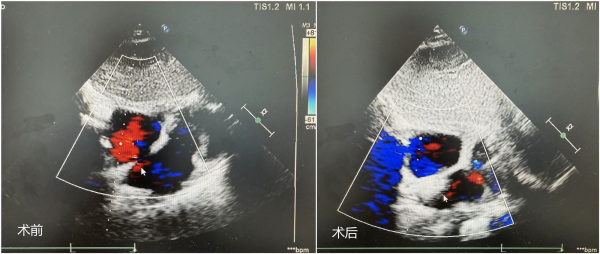

据了解,烟台市民李先生长期受反复头痛、头晕等问题困扰,口服药物治疗效果不佳。近期,他又被诊断出肾病、肾功能不全,今后可能需要进行透析治疗。为进一步查明病因,李先生接受了详细检查。超声检查发现其心脏存在房间隔缺损合并卵圆孔未闭,右心声学造影进一步证实心脏血流存在“右向左分流”。医生判断,李先生长期的头痛、头晕症状很可能与此心脏异常通道有关,同时,其后期若进行肾病透析,此心脏问题将显著增加血栓栓塞的风险。

经过多学科反复综合评估,烟台山医院北院心胸外科团队为李先生制定了周密的手术方案,并成功实施了经皮房间隔缺损合并卵圆孔未闭介入封堵术。整个手术过程顺利,耗时短。术后第二天,李先生即可下床活动,并于第三天康复出院。令他欣慰的是,术后不仅头痛、头晕症状明显改善,未来因肾病透析可能带来的栓塞风险也得以有效规避。